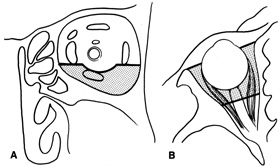

complete hemostasis. Indications Lateral orbitotomy provides excellent access to deep lesions in the subperiosteal, peripheral, or

intraconal space lateral to the optic nerve (Fig. 8A, B).  Fig. 8. Coronal (A) and axial (B) views in an illustration of areas (shaded) amenable to lateral

orbitotomy. Fig. 8. Coronal (A) and axial (B) views in an illustration of areas (shaded) amenable to lateral

orbitotomy.